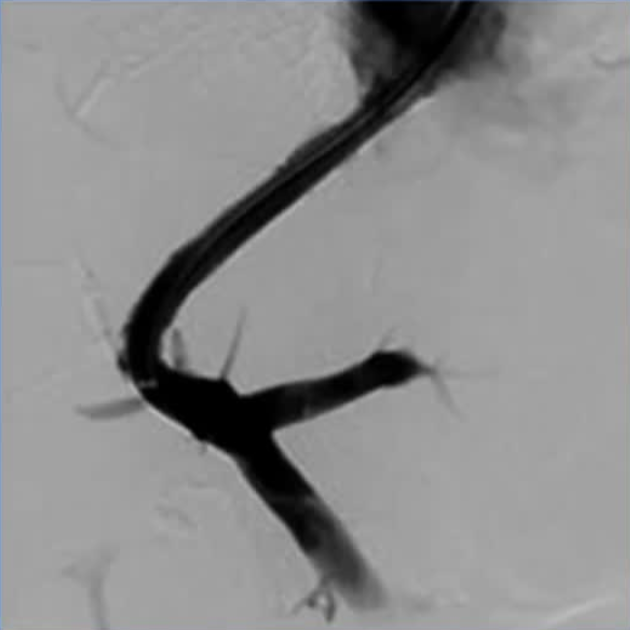

技术List

右侧的经颈静脉入口通道→ 10Fr鞘进入→ 右房压力测量→ 5Fr 导管进入右肝静脉→ 肝静脉造影和压力测量→楔形静脉造影及压力测量→ 进入门静脉通道→ 压力测量 →门静脉扩张术 →造影→ 血栓治疗→ 支架置入

关键步骤 :

楔肝静脉造影及压力测量、有限的价值,所提供的信息将取决于: 阻塞程度和 血栓范围

进入门静脉通道、难以确认的回抽血液位于门静脉内, 对造影剂注射时出现异常模糊,仅依赖“盲”导丝导航